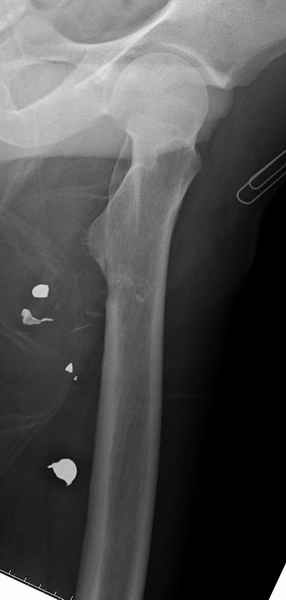

Больной с огнестрельным переломом бедра с вовлечением около 15% медиального кортекса, входное отверстие около 1 см в диаметре; стабильный, без сосудистых и неврологических признаков.

Литературные данные о влиянии кортикального дефекта на стрессовые переломы в длинных трубчатых костях в основном встречаются в онкологии, например кортикальный дефект более 50% имеет больше шанса стрессовых переломов, чем в нашем случае.